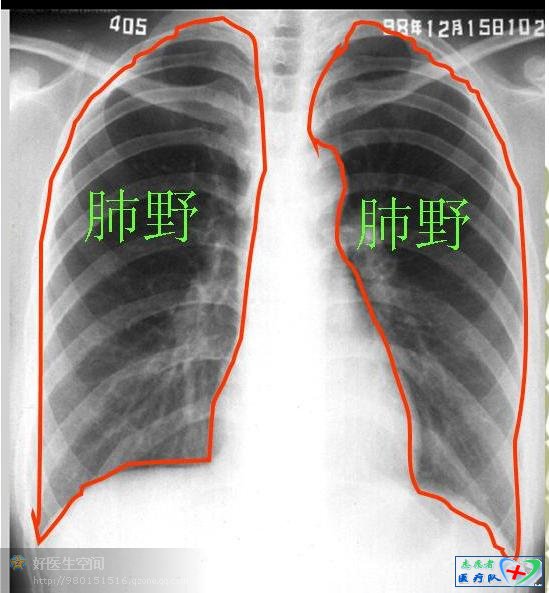

Effusions(双侧肺野)

青少年肺周围肺纹理不易看到,老年人可以看得到,但不宜渗透到肺的边缘。肺纹理主要由肺血管组成,在肺门附近,或内带见到细小密度较高的结节阴影可能是肺血管的横断面。任何原因引起支气管壁增粗,均可使肺纹理增强。肺纹理的走行代表代表肺叶及肺段的解剖学结构。肺纹理纤细是由肺泡增大或肺气肿引起。

我们知道一侧肺野从肺门到肺的外周分为三等份分别称为肺的内、中、外带,正常情况下肺内中带有肺纹理,外带无,如果外带出现了肺纹理则有肺纹理的增多,反之内中带透亮度增加则肺纹理减少。对肺内中外带的区分还有一个意义,那就是对肺气肿时肺压缩的判断,一般来说肺内中外带占肺的量分别为60%、30%、10%。